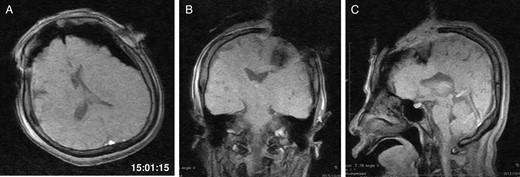

General anaesthesia was induced. Following left frontal craniotomy and dural incision, the first iMRI was performed (Fig. 1 ). One hundred fifty-eight minutes from induction, the patient regained consciousness after all anaesthetics were ceased. Tumour resection was performed with free conversation. However, after 143 min of surgery under the awake condition, the patient came to complain of excessive sleepiness though she could respond to verbal commands. Electrocorticogram (ECoG) did not detect after-discharge. The tumour was successfully removed en bloc fashion. Progressive brain swelling was not observed. The second iMRI was commenced 182 min into the awake phase (Fig. 2). Thirteen minutes from the beginning of the second iMRI scanning, the patient did not respond to noxious stimuli. When the patient was removed from the gantry, she was unconscious and had stopped spontaneous breathing. Her pupils were isocoria and did not dilate. Neither epileptic seizure nor anaphylactic reaction occurred. The peripheral oxygen saturation was not measurable, but cardiac instability or signs of vomiting were not observed. We decided to discontinue the operation under the awake status. No electrolyte imbalance or hypoglycaemia was observed. Subsequently performed iMRI identified a thin subdural haematoma in the contralateral side (Fig. 3). The fourth iMRI confirmed that most of the haematoma was evacuated following right frontal craniotomy.

The second iMRI was performed after the tumour resection. (A) Axial, (B) coronal and (C) sagittal T1-weighted scout images show no intracranial haemorrhage. The time of scan is superimposed.